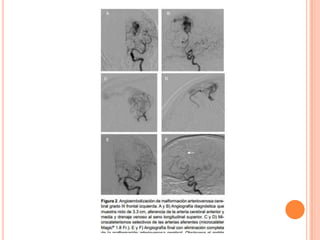

a. Tomografía computada con contraste

que muestra malformación arterio-

venosa temporal derecho.

b. En la angiografía carotídea derecha

se observa malformación arteriovenosa

temporal derecha que recibe suplencia

vascular de la arteria pericallosa.

c. En incidencia frontal se muestra

el control postembolización de MAV

cerebral.

d. En incidencia oblicua pre embolización.

e. Control postembolización en incidencia

oblicua.

f. Control preembolización en incidencia

lateral.

a. Tomografía computadacon contraste que muestra malformación arterio- venosa temporal derecho. b. En la angiografía carotídea derecha se observa malformación arteriovenosa temporal derecha que recibe suplencia vascular de la arteria pericallosa. c. En incidencia frontal se muestra el control postembolización de MAV cerebral. d. En incidencia oblicua pre embolización. e. Control postembolización en incidencia oblicua. f. Control preembolización en incidencia lateral.